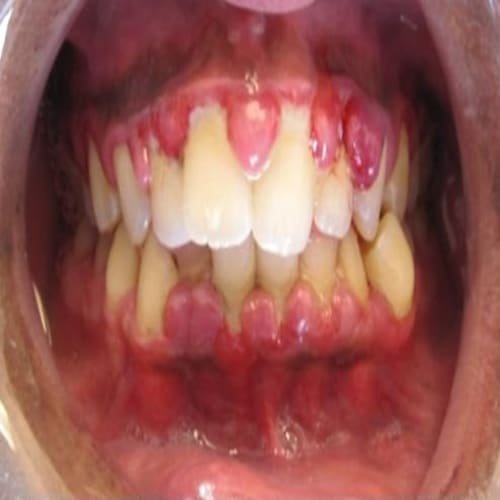

Gingivitis atau gusi bengkak merupakan suatu inflamasi atau peradangan yang mengenai jaringan lunak di sekitar gigi atau jaringan gingiva.

Umumnya terlihat inflamasi atau peradangan yang mengenai jaringan lunak di sekitar gigi atau jaringan gingiva disebut gingivitis. Kondisi kronis maupun akut dapat menghasilkan perubahan pada konsistensi gingiva normal yang kaku dan tegas. Peradangan gingiva terjadi resesi ke apikal menyebabkan celah menjadi lebih lebar dan meluas ke permukaan akar.

Tanda klinis: Adanya kemerahan (hiperemi sudah terlihat ) terjadinya pendarahan pada saat probing . Histologi: infiltrasi leucosit dalam jaringan konektive dibawah junctional epitelium leukasit +_ 75% dan netrofil yang bermigrasi sebagai mana juga sel-sel plasma.

Gingivitis tahap III

Bertambah beratnya lesi inflamasi, aliran darah bertambah lambat, warna gingiva menjadi merah kebiruan. Perbedaan gingivitis tahap II dan III meningkatnya jumlah sel plasma yang berubah menjadi sel inflamasi sel plasma akan menginvasi ke konective tissue tidak hanya dibawah junctional epitelium, akan tetapi ke jaringan yang lebih dalam sekitar pembuluh darah terjadinya pelebaran pada junctional epitelium dan pada ruangan interseluler diisi dengan granuler seluler yaitu lisosom yang berasal dari netrofil yang hancur, limfosit dan monosit, lisosom ini mengandung asam hidrolase yang dapat merusak komponen jaringan. Aktivitas genolitic meningkat pada inflamasi jaringan gingiva oleh enzim kologenase.

Gingivitis adalah bentuk penyakit periodontal paling ringan. Ini menyebabkan gusi menjadi merah, bengkak, dan mudah berdarah. Biasanya ada sedikit atau tidak ada rasa tidak nyaman pada tahap ini. Gingivitis sering disebabkan oleh kebersihan mulut yang tidak memadai. Gingivitis dapat disembuhkan dengan perawatan profesional dan perawatan di rumah yang baik.